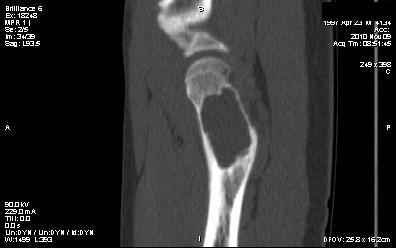

Мальчик 13 лет. В течение нескольких месяцев беспокоят боли в левом тазобедренном суставе.

При обследовании выявлена киста шейки левого бедра с сопутствующими изменениями в головке бедра, которые мы трактуем как дистрофические. Планируем вскрытие и санацию полости кисты передне-боковым доступом, костную пластику. Перед нами возникли следующие вопросы: для пластики использовать крыло подвздошной кости либо большеберцовую кость,либо их комбинацию, (полость большая,одним крылом можно не обойтись) или донорский аллотрансплантат с Коллапаном? Фиксировать ли? Если фиксировать, то чем? Доступны обычные угловые пластины либо АВФ.

Выполнили, что и запланировали. Обошлись одним крылом. Зафиксировали пластиной. Мысль о возможной фиксации TEN приходила, но... доступны только гвозди Эндера. А ими - не решились.